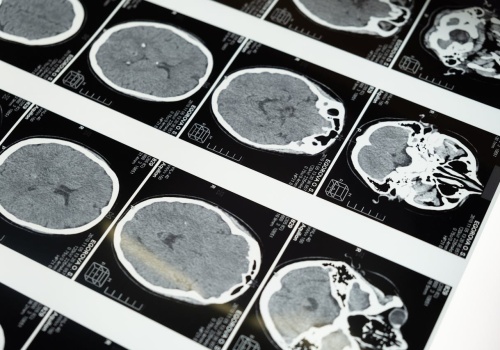

Kumulacja ołowiu w kościach może niemal trzykrotnie zwiększać ryzyko choroby Alzheimera – wynika z nowych badań. Artykuł Nowe dowody: ekspozycja na ołów zwiększa ryzyko demencji i choroby Alzheimera pochodzi z serwisu Alert Medyczny.

Ekspozycja na promieniowanie przed ciążą może zwiększać ryzyko poronienia i wad wrodzonych

Tomografia komputerowa wykonana przed ciążą może zwiększać ryzyko poronienia – wynika z badania obejmującego ponad 5 mln ciąż. Artykuł Ekspozycja na promieniowanie przed ciążą może zwiększać ryzyko poronienia i wad wrodzonych pochodzi z serwisu Alert...